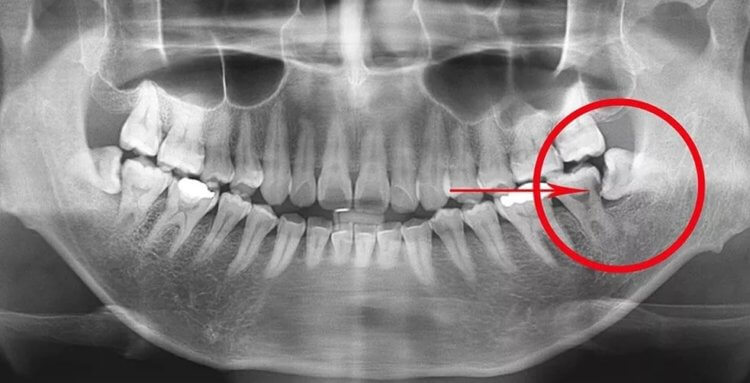

Таким образом получается, что современным людям просто не повезло. Все мы имеем относительно плоские лица с небольшими челюстями. Поэтому ждать появления зубов мудрости иногда приходится очень долго. Но иногда «восьмерки» поступают очень подло и начинают резаться даже на небольших челюстях. Они буквально толкают уже имеющиеся зубы снизу и иногда даже остаются внутри десны. В таких случаях человек испытывает далеко не самые приятные чувства, поэтому стоматологи простоту их удаляют. Всего у человека может вырасти четыре зуба мудрости, но у некоторых людей их нет — рентген не обнаруживает даже их зачатков.

Зуб мудрости на рентгене